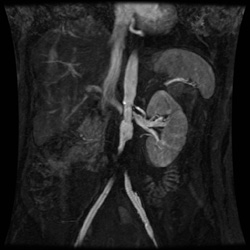

RADIOLOGY: GENITOURINARY: GU: Case# 34235